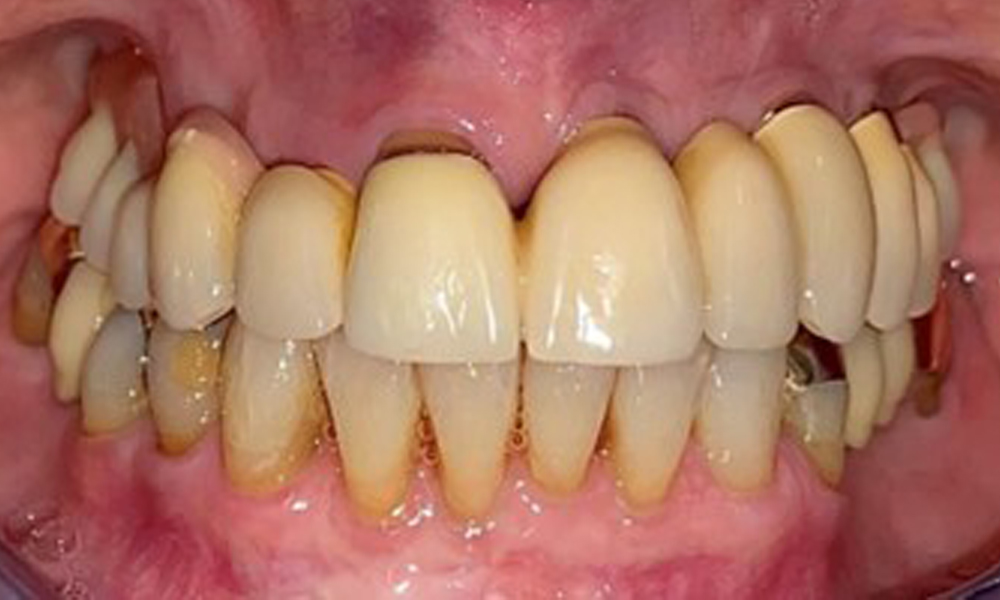

The patient was fitted with a combined removable maxillary telescopic prosthesis more than 25 years ago (Fig. 1, Fig. 2, Fig. 3) and is very happy with her dentures. The patient has an adequate fixed denture for the mandible (Fig. 4).

Frontal view with the maxillary denture in situ.

Fig. 1: Frontal view with the maxillary denture in situ.